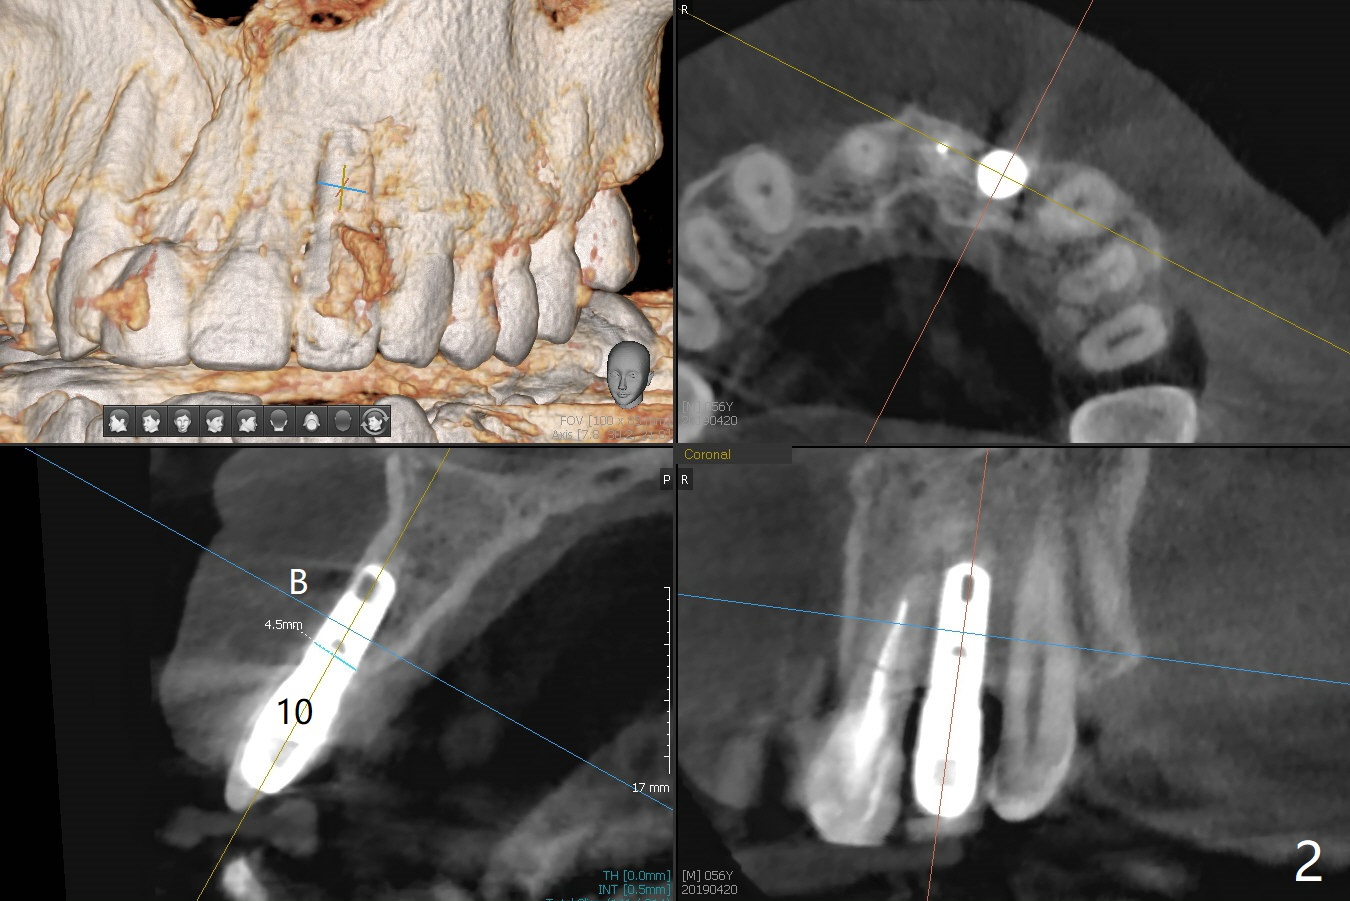

A 56-year-old man presents to clinic for recementation of the crown/post at #8, which is non-salvageable (Fig.1). There are 3 existing implant crowns, including #10. The implant at #10 (4.5 mm in diameter) was placed buccally, although there is no infection (Fig.2). To prevent this complication, a smaller implant should be placed palatal (Fig.3). In addition, the tooth #7 is missing. Instead there is a labial concavity (Fig.3 *). Use a temporary abutment for provisional.